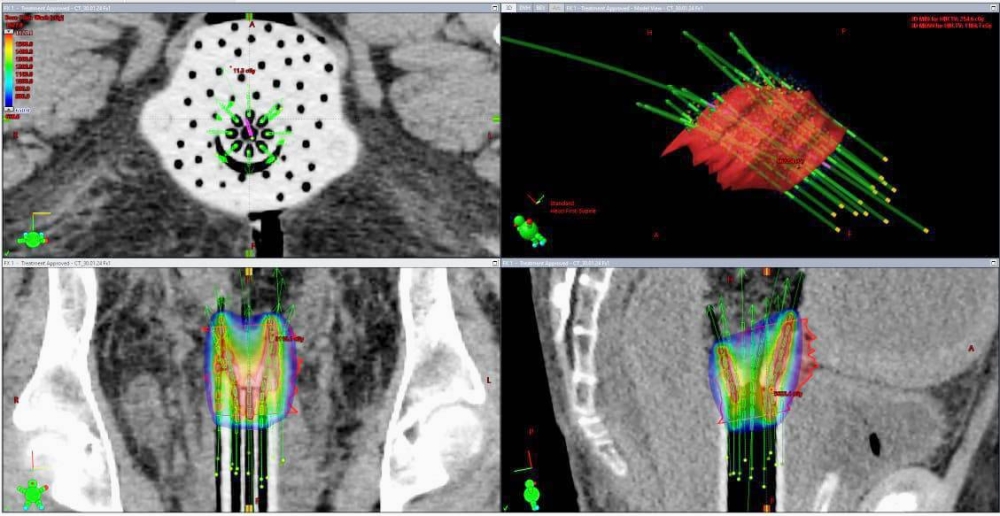

نجح فريق طبي بمدينة الملك فهد الطبية، عضو تجمع الرياض الصحي الثاني، في إجراء عملية نادرة جداً لسيدة في عمر الستين عاماً، تعاني من سرطان عنق الرحم من المرحلة المتقدمة بالحوض، بحجم ٧ سنتيمترات، باستخدام زرع الإبر الجراحية لإيصال المادة المشعة لمكان الورم المتبقي بعد العلاج الإشعاعي والكيماوي.

وأوضحت المدينة الطبية، أنها أول حالة نادرة يتم علاجها بهذه الطريقة لصعوبة مكان الورم، وتعطى الجرعة اللازمة للقضاء على السرطان وزيادة نسبة الشفاء لأكثر من ٨٠٪. وكشفت المدينة، أنه وبعد عمل الفحوصات والصور المغناطيسية للحوض بعد إعطائها العلاج الإشعاعي الخارجي والعلاج الكيماوي تبيّن وجود جزء كبير من الورم لم يتم القضاء عليه بواسطة العلاج الخارجي. وأوضحت، أنه في مثل هذه الحالات المرضية المعقّدة لا يجد المريض خيارات علاجية متعددة ويكون أمام خيارين، إمّا العلاج عن طريق الجراحة المعقدة أو زرع الإبر الجراحية، وهو الخيار الأنجع، وسيكون على المريض تكبد عناء السفر بحثاً عن هذا العلاج خارج المملكة. وأبانت المدينة، أنه بالدعم الذي يحظى به القطاع الصحي وبكوادرها الوطنية المؤهلة والمتخصصة بالأورام والعلاج الإشعاعي والفيزياء الطبية والتمريض والتخدير، تم علاج المريضة وزراعة الإبر الجراحية لإيصال المادة المشعة لمكان الورم، وتم تحديد الجرعة اللازمة والقضاء عليه، والسيدة تتمتع بصحة جيدة بين أهلها وفي وطنها.